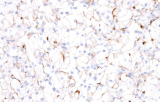

L'immunoistochimica (IHC) rimane un metodo centrale in ematopatologia perché fenotipi diagnostici significativi possono essere risolti direttamente nell'architettura tissutale, utilizzando marcatori di lignaggio, differenziazione e proliferazione definiti da anticorpi. Per qualsiasi anticorpo CE-IVD o anticorpo IHC destinato a flussi di lavoro di ricerca clinica/diagnostica, la pratica basata sull'evidenza enfatizza la validazione analitica e il controllo delle variabili preanalitiche e analitiche per garantire risultati accurati e riproducibili.

- Linfoma di Hodgkin classico: le cellule tumorali sono tipicamente CD30+ e spesso CD15+, con PAX5 debole e CD20 negativo nelle grandi cellule tumorali.